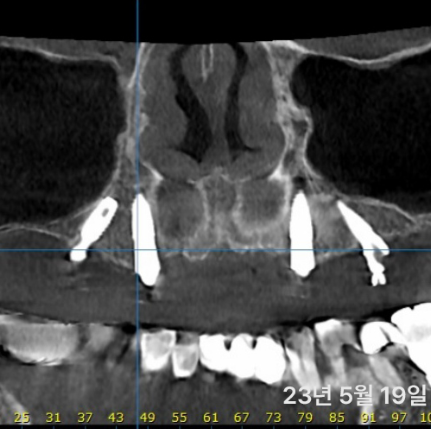

골질이 좋은 경우 고정이 30이상 나오는 경우엔 가능해요.

하지만 사진처럼 사람마다 골질이 다양해서 무리하면 탈이 날수 있습니다. 개인에 따라 달라요.

Fig.18.12 The four macroscopic bone qualities are (A) D1 (arrow), (B) D2, (C) D3 (arrow), and (D) D4. The bone-density variance is dependent on ana-tomic location and the local strain history of the bone after tooth loss.